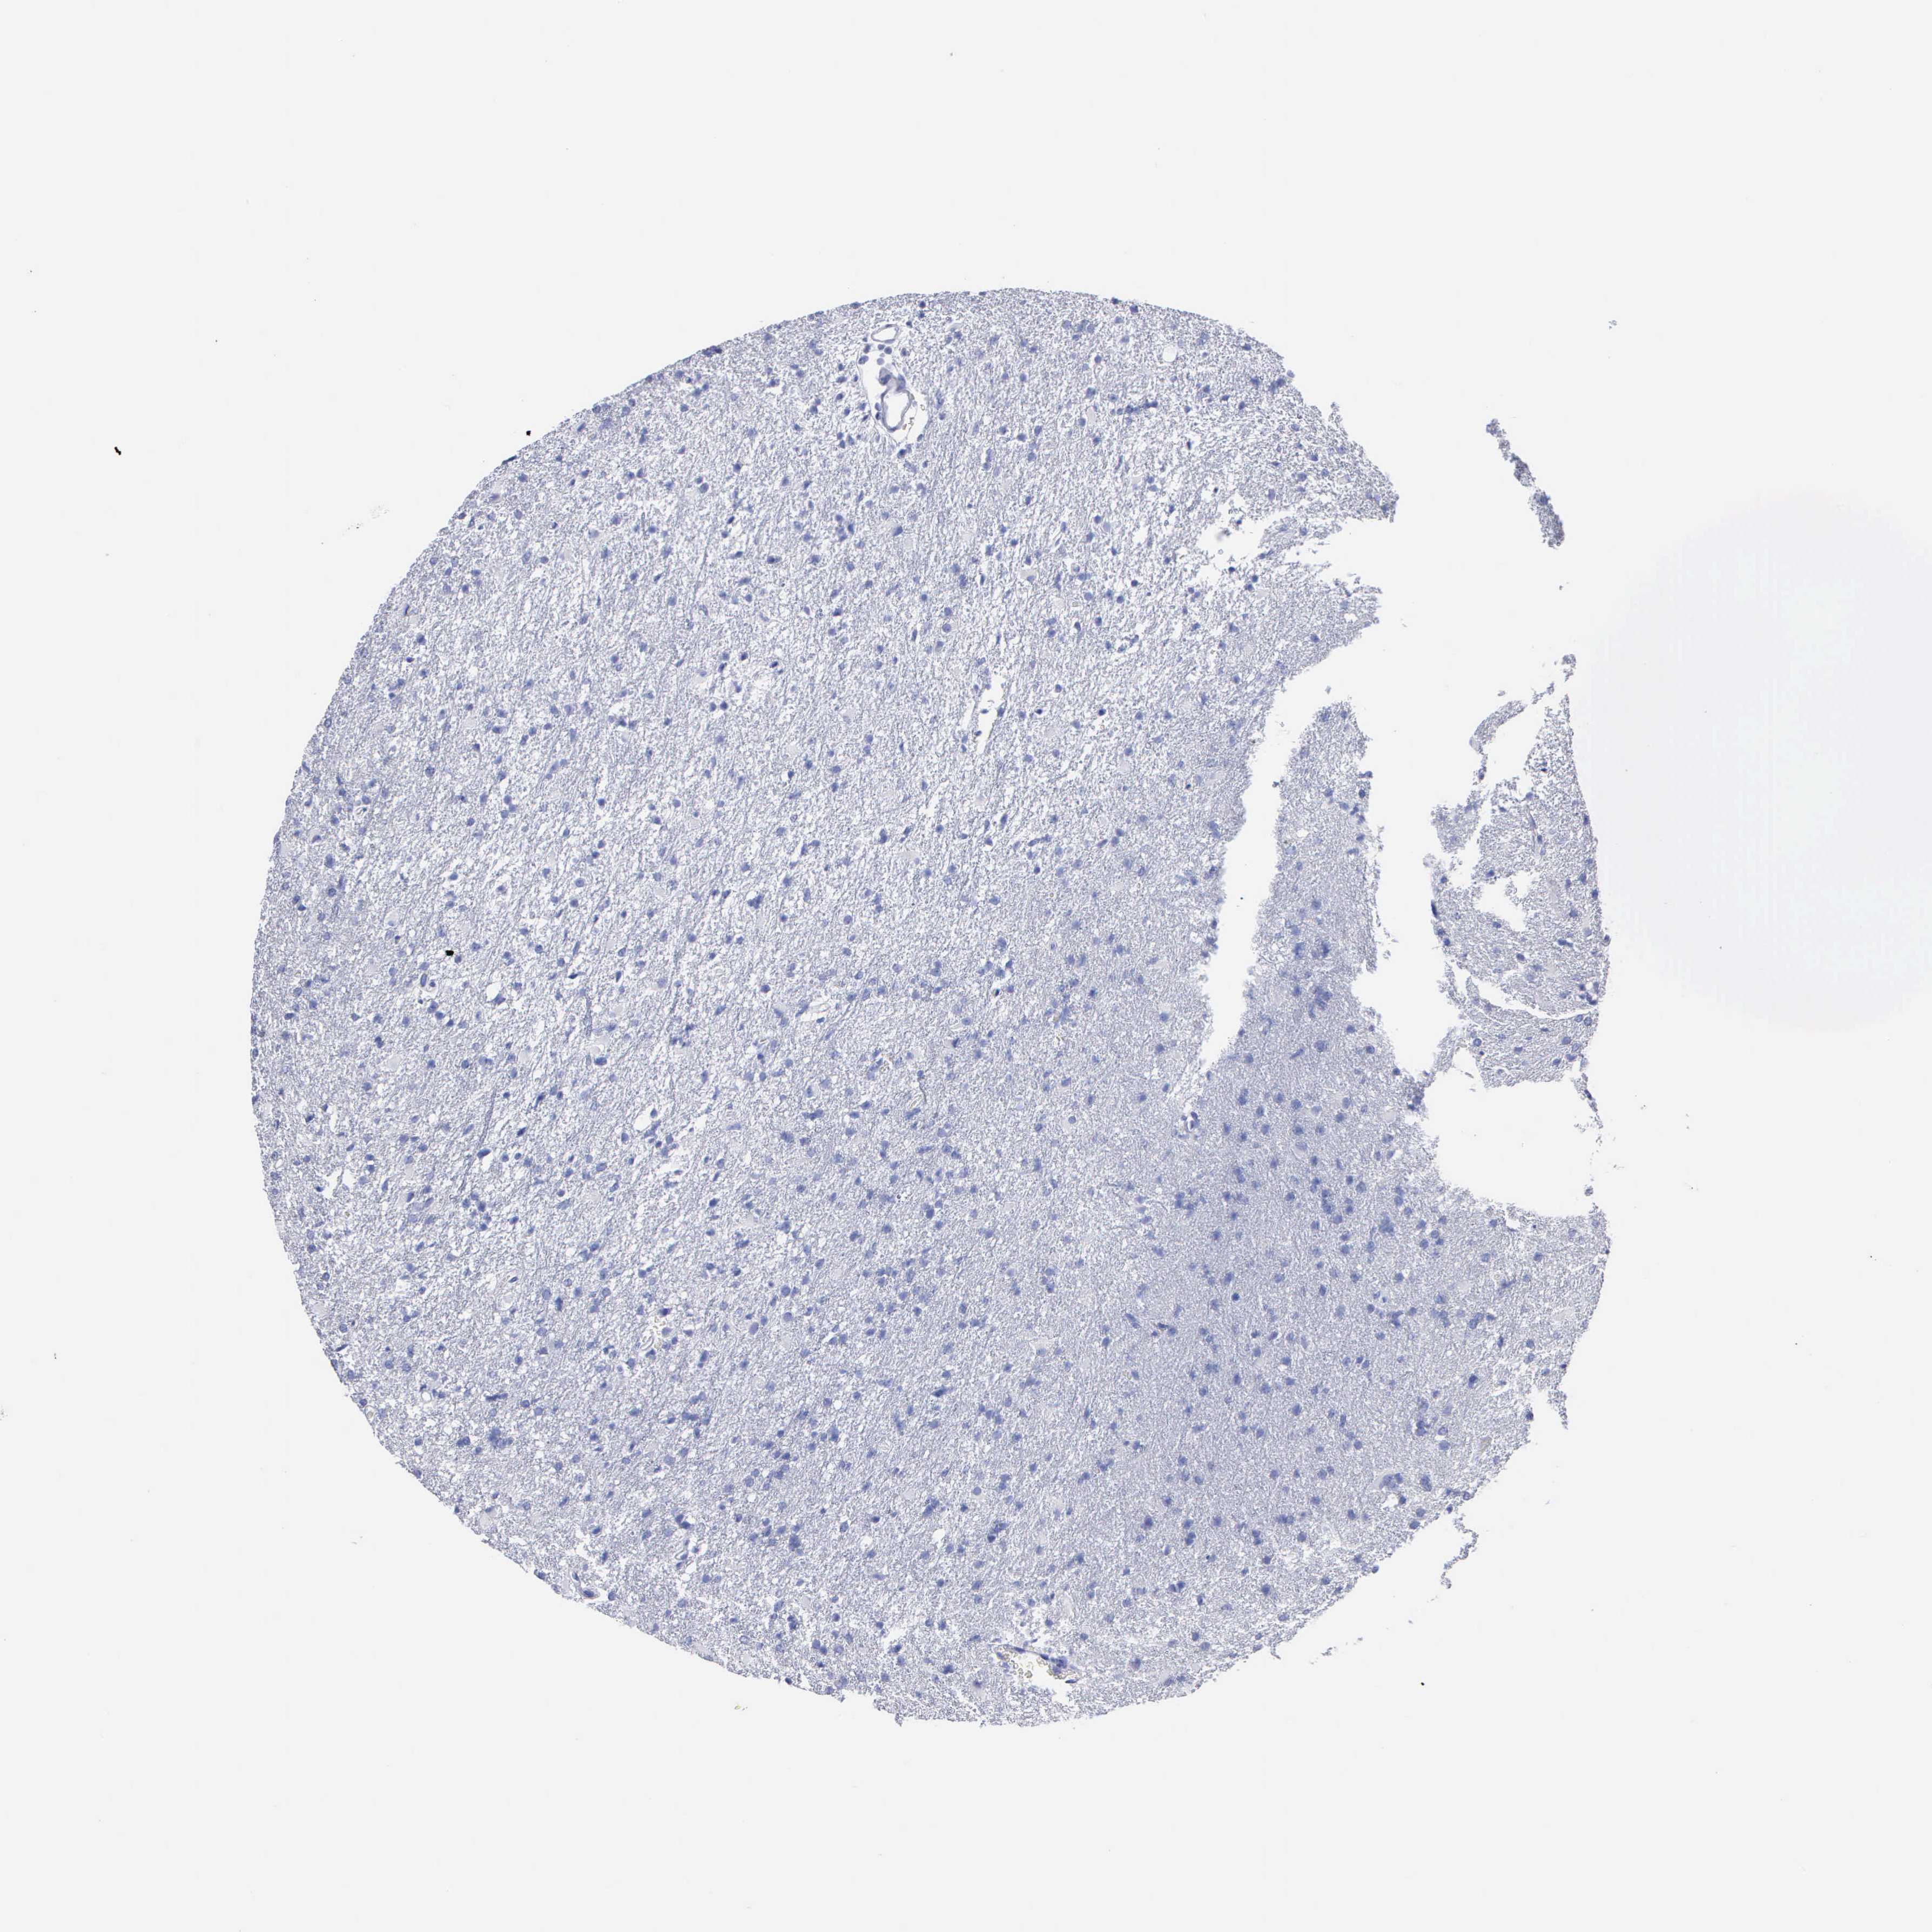

GLIOMA - Protein expressioni

A mouse-over function shows sample information and annotation data. Click on an image to view it in a full screen mode. Samples can be filtered based on level of antibody staining by selecting one or several of the following categories: high, medium, low and not detected. The assay and annotation is described here.

Note that samples used for immunohistochemistry by the Human Protein Atlas do not correspond to samples in the TCGA dataset.

Antibody stainingi

Antibody staining in the annotated cell types in the current human tissue is reported as not detected, low, medium, or high, based on conventional immunohistochemistry profiling in selected tissues. This score is based on the combination of the staining intensity and fraction of stained cells.

Each image is clickable and will lead to virtual microscopy that enables deeper exploration of all samples and also displays staining intensity scores, fraction scores and subcellular localization as well as patient and tissue information for each sample.

Antibody HPA047737

Antibody CAB000110

Glioma, malignant, High grade

Glioma, malignant, Low grade